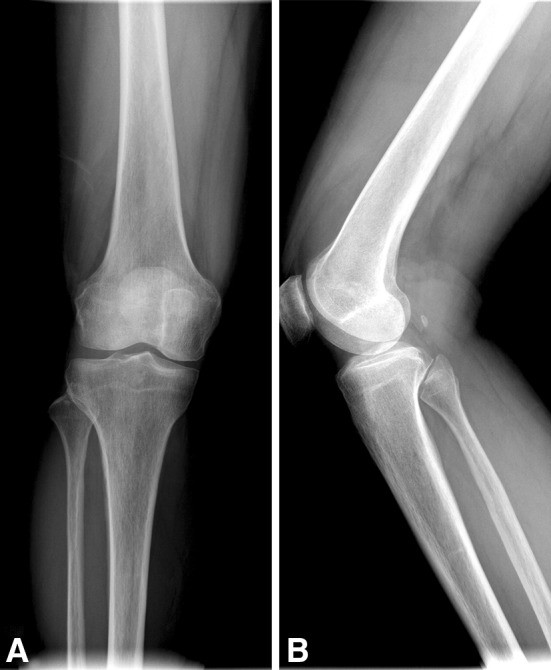

After initial AP and lateral radiographic evaluation (Fig. 1), the patient underwent MRI of the right knee (Figs. 2, 3).

Fig. 1A–B.

(A) AP and (B) lateral radiographs of the right knee show a radiolucent soft tissue lesion with fat attenuation in the anterolateral aspect of the knee.

AP (Fig. 1A) and lateral (Fig. 1B) radiographs of the right knee showed a radiolucent soft tissue mass in the anterolateral aspect of the knee. There was no visible bone destruction or other lesion identified. MRI revealed one large soft tissue mass in the suprapatellar pouch that had the same signal intensity as the subcutaneous fat and an internal septum with low signal intensity on T1- and T2-weighted sequences within it (Fig. 2A–C). Minimal joint effusion outlining the joint capsule also was seen on an axial proton density fat saturation image (Fig. 2D). The soft tissue lesion also showed mild peripheral enhancement pattern on postgadolinium T1-weighted MRI (Fig. 3).